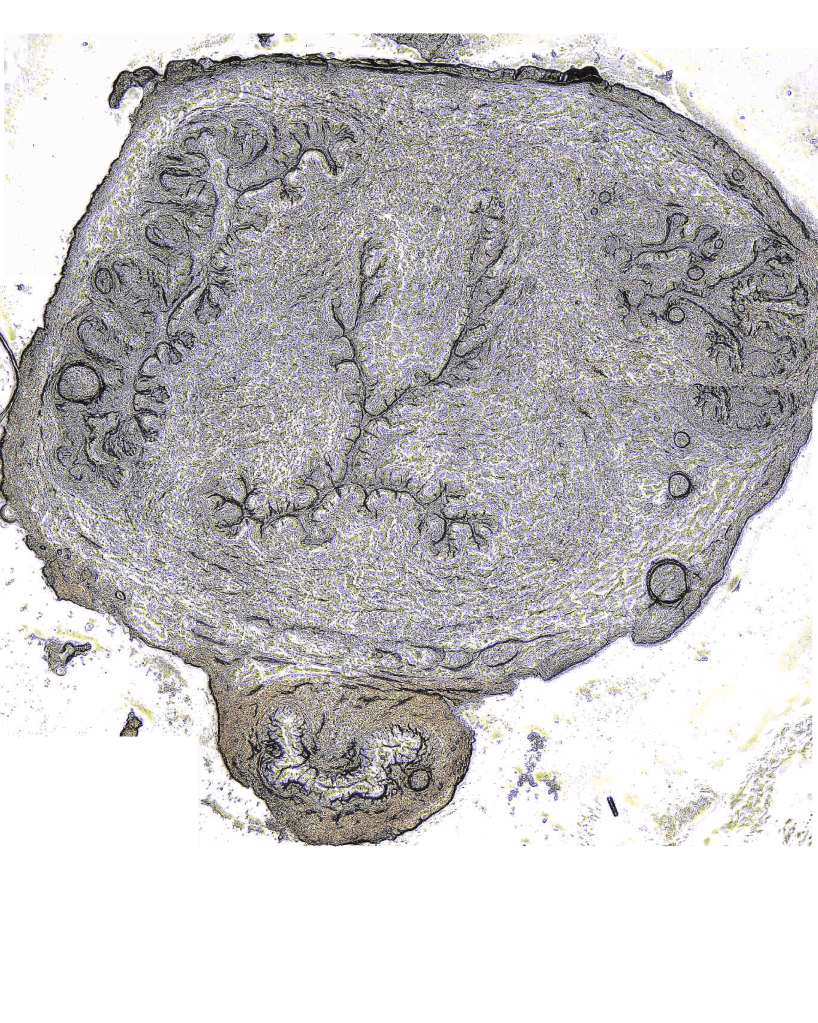

Mapping the Human Uterus

The uterus undergoes dramatic cellular and extracellular matrix growth and remodeling throughout the course of pregnancy and in the context of many gynecological diseases. We seek to characterize the multi-scale time-dependent mechanical properties of the uterus in healthy and pathological nonpregnant and pregnant states, utilizing nanoindentation, macro-scale indentation, and tensile testing.